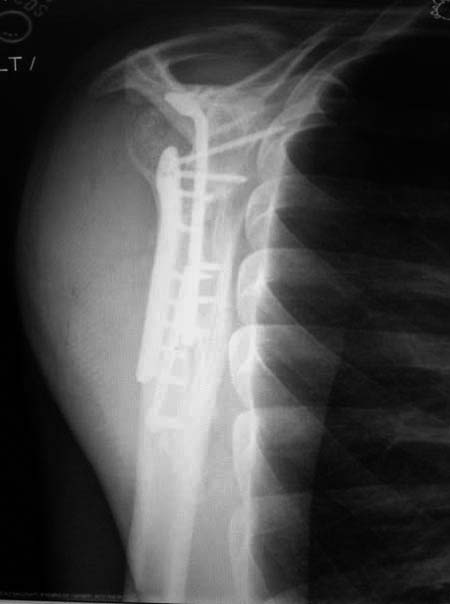

Здесь пример, стандартные снимки: плечо и лопатка прямой снимок,

аксиллярный и косой снимки (Y-view) и фиксация пластинами по краям, где

имеется более твердая кость. Специальные пластины, хотя любая 2.7 или

3.5 мм тубулярная пластина подойдут для фиксации перелома. Риск операции

- это повреждение нерва во время доступа и ре-фиксация ротаторной

манжетки если потребуется широкий доступ!